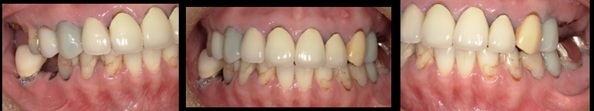

50代女性重度歯周病 抜歯即時GBR(骨造成)・FGG(角化歯肉移植)・インプラント

治療前

治療後

施術名 | 抜歯即時GBR(骨造成)・FGG(角化歯肉移植)・インプラント |

主訴 | 歯が揺れている噛みにくい |

施術の副作用(リスク) | オペの感染。インプラント周囲炎 |

施術の価格 | GBR(骨造成)5万・FGG(角化歯肉移植)5万・インプラント35万 |

コメント | 重度歯周病のため残るとこは残してどうしてもだめなところは抜歯しインプラントをしました。骨がないためしっかり骨を作り、角化歯肉移植もししっかり長期保つような歯周外科を施しました。 |